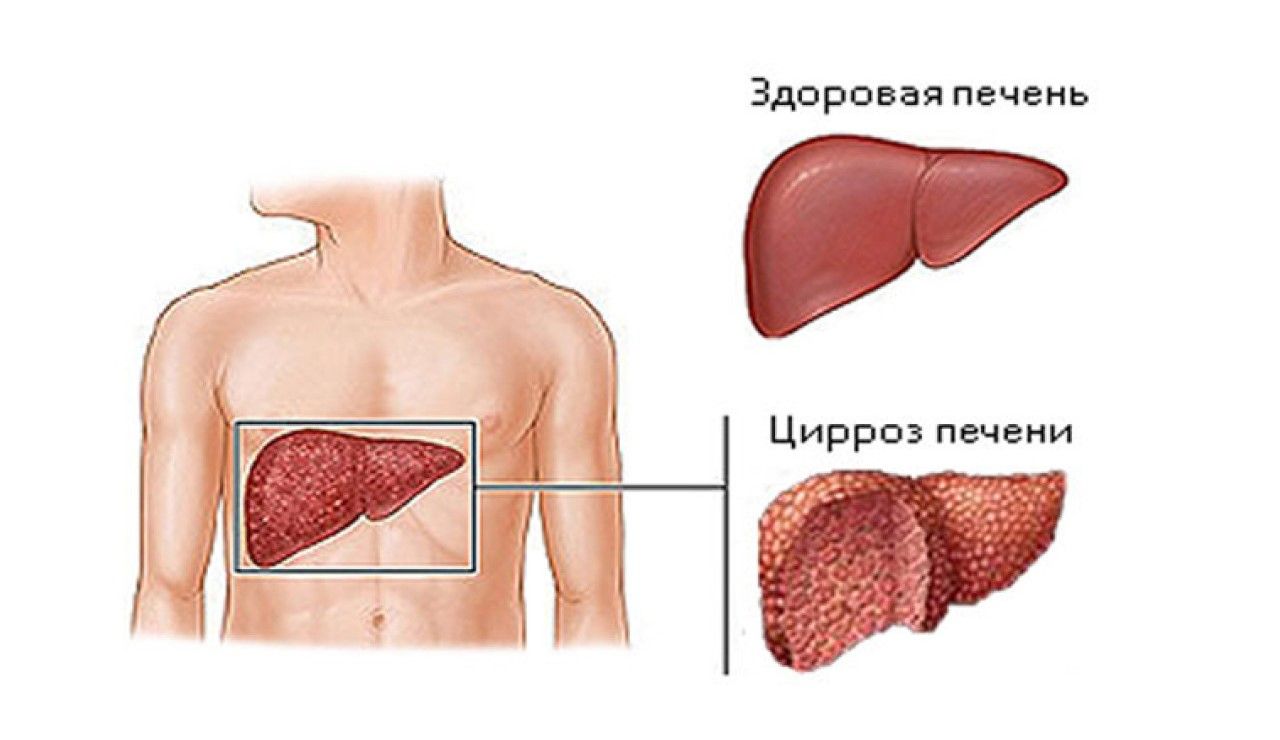

Изображения заболеваний печени: признаки и симптомы